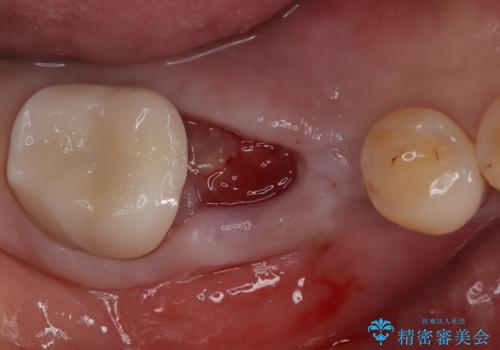

- 奥歯の欠損をインプラントで治療したいと来院された患者様です。

骨の状態が安定するまで待機したのち、インプラントを埋入しています。